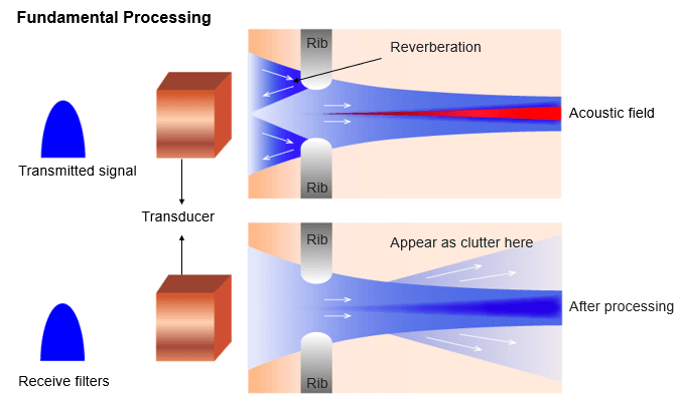

Reverberation Artifacts

What is a reverberation artifact?

Reverberation artifact occurs when the ultrasound beam encounters two highly reflective structures. It reflects between lungs, ribs, and skin. When the ultrasound beam reflects back and forth between the highly reflective structures, the ultrasound transducer interprets the sound waves returning as waves returning from deeper depth since it took longer for the wave to return to the transducer.

As they are of low energy (mostly equal to f0), they never develop harmonics. Therefore, receiver filters tuned at harmonic frequency remove reverberations at f0 and clean up the image.